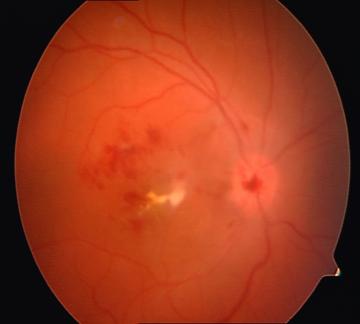

Examenul biomicroscopic al fundului de ochi evidentiaza la OD (fig.2) opacitati vitreene albe focale cu fenomene de vitrita reactiva ;papila decolorata, edematiata, proeminenta, cu contur sters , macular si interpapilomacular observandu-se focare inflamatorii confluente,alb-galbui ,imprecis delimitate, proeminente , precum si edem retinian.Vasele sangvine retiniene sunt de aspect normal.

Fig.2 FOD la internare